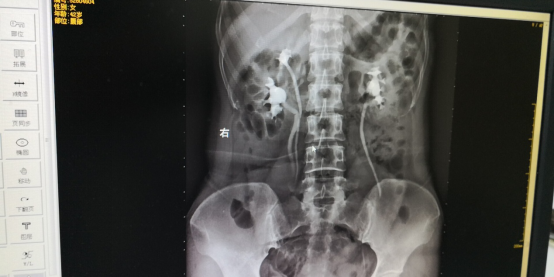

入院后经完善相关诊断,CT提示左右侧均有两套肾盂,左侧输尿管扩张积水。确诊为双侧重复肾畸形。因患者左侧的重复肾已有明显积水现象,手术指征明显,但要为其做手术治疗必须考虑保护其正常肾脏。因已带着四个肾脏系统生活多年,切除的时候容易出血且缝合难度大,经泌尿外科黄斌主任主持多次讨论治疗方案,决定采取腔镜微创手术,减少对患者的创伤。2018年2月21日在我院泌尿外科、麻醉科、手术室密切协作下,由泌尿外科宋志东副主任医师带领窦红珍主治医师执行手术,在未阻断肾血流的情况下,历时4小时。顺利实施了我市首例经腹腔镜左肾重复肾上半肾切除+左侧重复输尿管全段切除术。

CT检查可清晰显示重复肾畸形及合并积水的双输尿管, 能更清楚的显示重复肾的内容,同时CT连续层面观察可确定输尿管的异位开口,但对无扩张的重复输尿管显示不够清晰,直观。